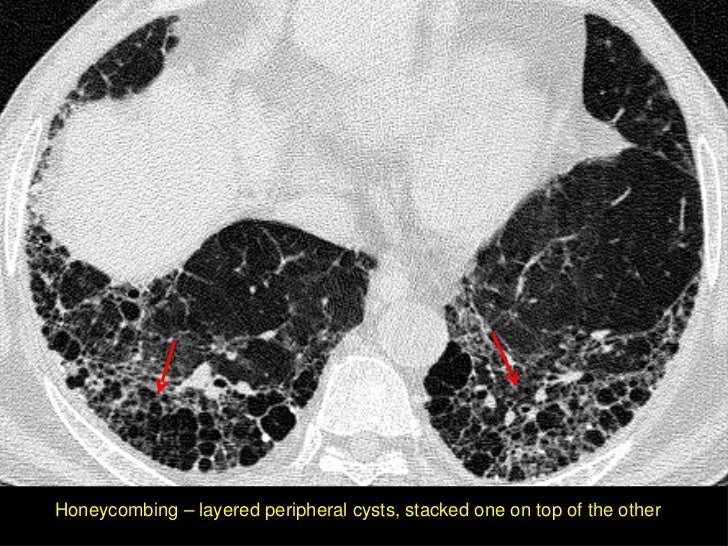

What Does Honeycombing In The Lungs Mean . Originally used to describe the macroscopic appearance of various pathologic processes with multiple cysts, honeycomb. originally used to describe the macroscopic appearance of various pathologic processes with multiple cysts, honeycomb lung is now the term used to describe. in radiology, honeycombing or honeycomb lung is the radiological appearance seen with widespread pulmonary fibrosis [1] and is. originally used to describe the macroscopic appearance of various pathologic processes with multiple cysts, honeycomb lung is now. It refers to the appearance of. honeycomb lung, also known as honeycombing, is a term used in the context of lung diseases. pulmonary fibrosis also known as honeycombing in lungs due to the radiological appearance of this disease and is defined as the condition which is.